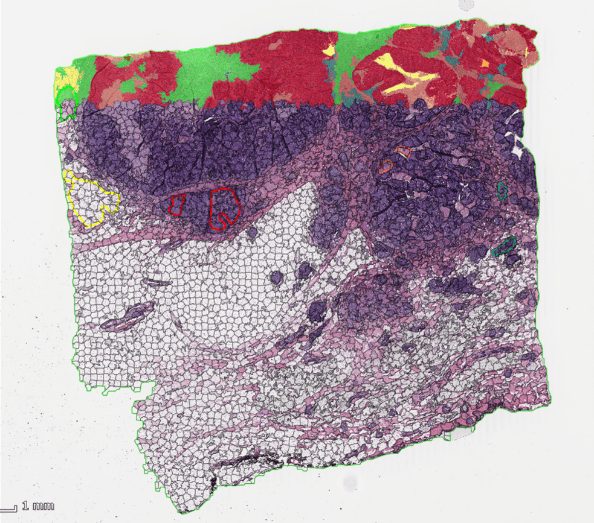

MICAIA_Monitor_heatmap

该应用程序对细胞类型之间进行空间分析。它将样本解释为一个图行,其中细胞是节点,细胞与细胞间的连接是边缘。每个细胞与相邻的连接在一起。然后对相邻的两种细胞类型进行连接分类。根据需要,可以通过提供最大距离的完全切断或基于连接细胞的平均长度和标准偏差来过滤长连接。最后,将连接细胞绘制为矩形图并显示在矩阵表中,其中每个列和行对应于一个源和目标细胞类型。

细胞对细胞连接分析